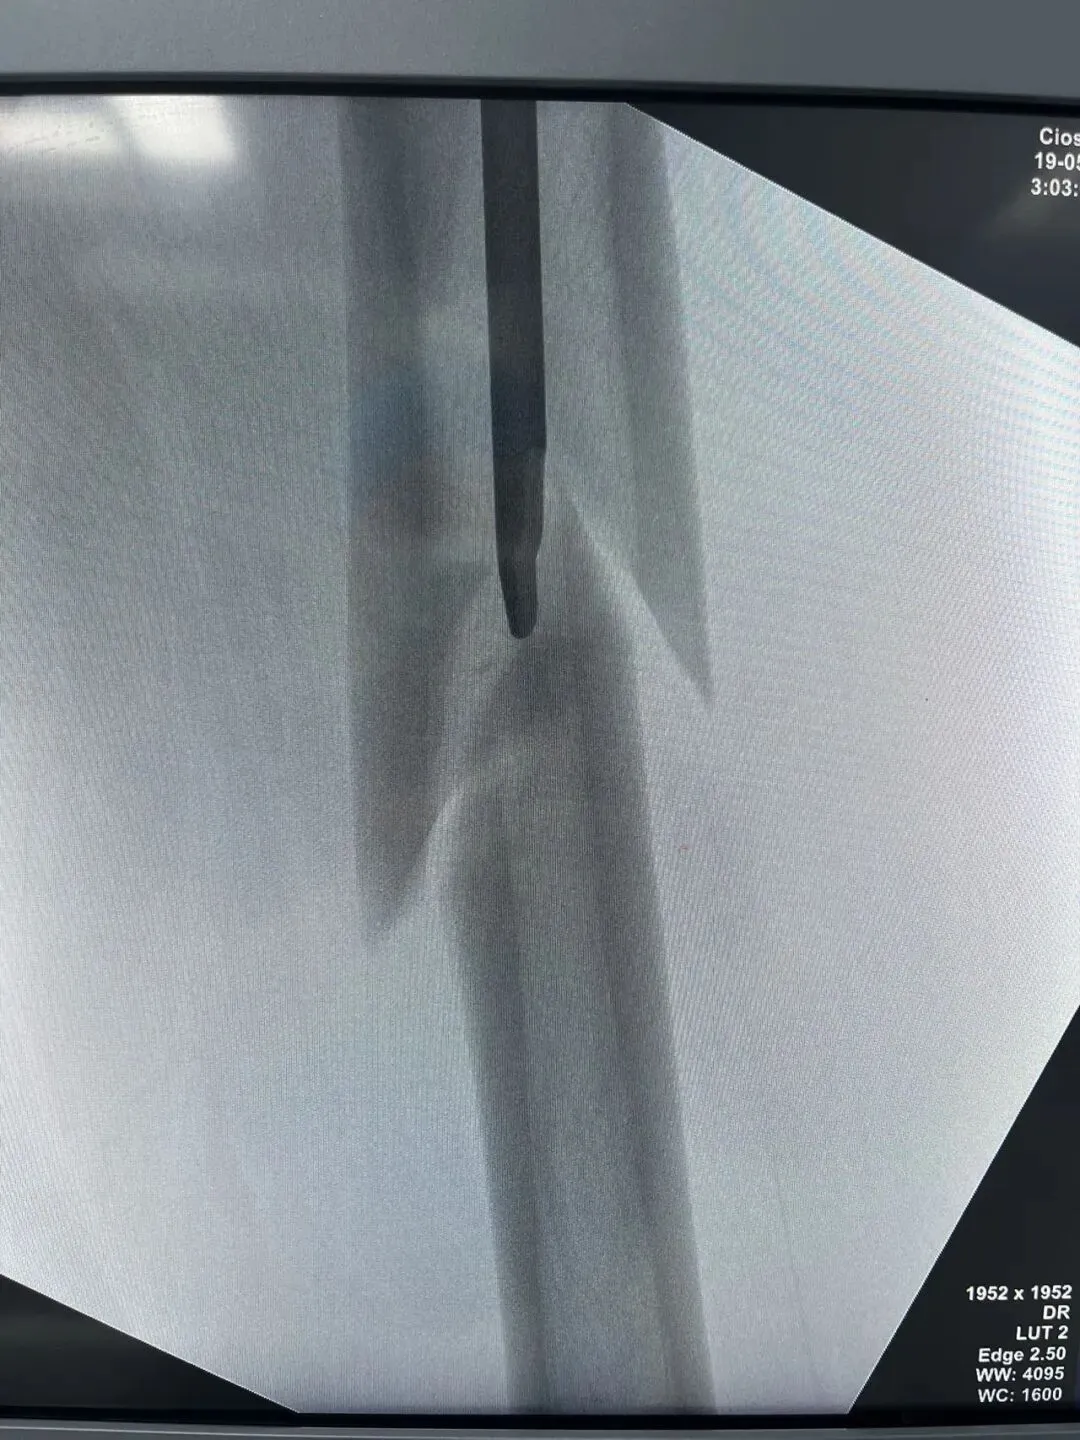

先看片子

中老年男性,高处坠落伤,如此长节段股骨近端骨折比较少见。手术治疗是必须的,患者等待期间血栓风险极高。而且患者卧床骨牵引期间护理极其不方便,给家人造成很大困惑为早点解决患者病痛,入院后积极抗凝预防血栓,伤后第3天手术治疗。我们选择PFNA闭合复位内固定。手术还算顺利。

手术在牵引床上操作,近端开口器开口后用金手指找远折端,找到后顺势插入导针,剩下的就是套路了。如此长节段的股骨近端骨折,一定要做到闭合复位,保证骨折周围软组织铰链夹板完整,不破坏局部血运,才能保证骨折的顺利愈合。

术后侧位看骨折块间仍有较大距离,但是我们不担心,骨折力线、颈干角没有太大问题。